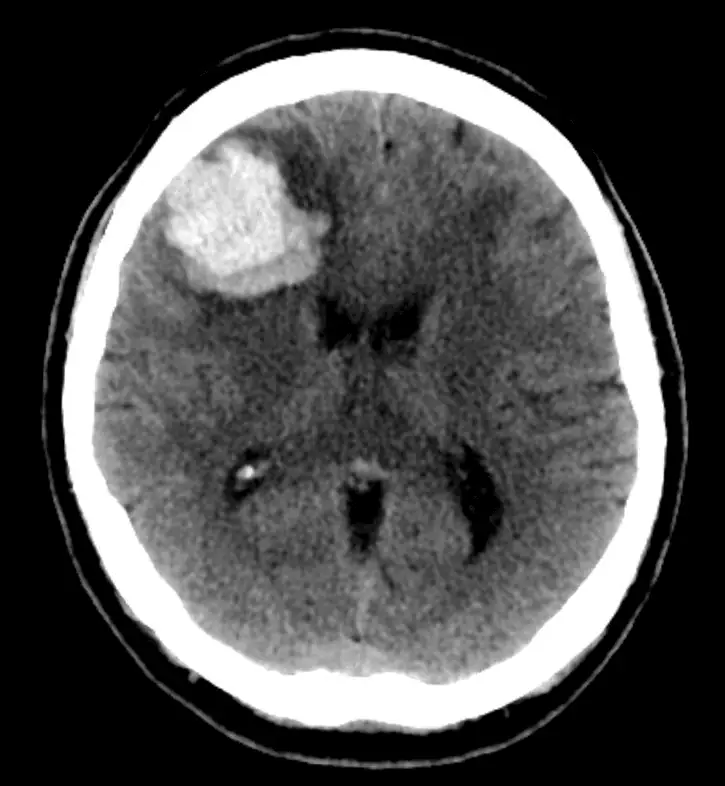

Brain non-contrast CT: Hypertension history and rapid start of left facial droop. What does the picture depict?

A significant high-density area caused by severe bleeding can be seen in the right frontal lobe in the picture. Since there was no contrast on the CT, this cannot be an enhancing mass.

Its location suggests that it is intra-axial rather than extra-axial in the brain, ruling out subarachnoid and subdural bleeding..

The calcified choroid plexus, a common occurrence, is the focus of high density in the posterior horn of the right lateral ventricle.